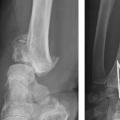

Au terme de ce bilan clinique, des radiographies standard du poignet avec 4 incidences sont incontournables : face et profil stricts et, trop souvent oubliés, de trois quarts latéral et médial. Ces dernières incidences sont en particulier utiles pour analyser l’étendue de la comminution métaphysaire dans le plan horizontal et pour dépister les refends articulaires.8

L’analyse précise et détaillée des clichés radiographiques renseigne sur les critères morphologiques importants détaillés plus haut : l’inclinaison frontale, l’inclinaison sagittale et l’index radio-ulnaire distal. Il faut également apprécier les caractéristiques métaphysaire et épiphysaire de la fracture et la présence de lésions associées : comminution, nombre et déplacement des fragments articulaires, fractures de l’extrémité inférieure de l’ulna, fractures des os du carpe, lésions ligamentaires intracarpiennes ou de l’articulation radio-ulnaire distale.